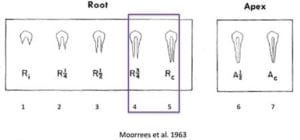

De prognose is een voorspelling van de mogelijke te verwachten uitkomst. Er zijn verschillende factoren die je kan gebruiken om de prognose te bepalen aan de hand van klinische factoren, omgevingsfactoren, lokale factoren en restauratieve factoren, zoals hieronder weergegeven.

Klik hier voor een vergrote afbeelding

Wanneer er sprake is van een goede prognose is het zinvol om het element te behandelen. Wanneer er sprake is van een licht dubieuze prognose is het waarschijnlijk zinvol om het element te behandelen. Bij een matige prognose is het twijfelachtig of het element succesvol te behandelen is en bij een slechte prognose is het niet zinvol om te behandelen.